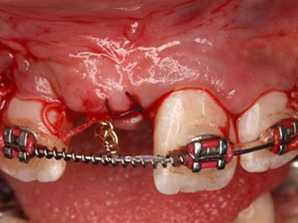

Răng thừa (a) làm R11 (b) bị kẹt không mọc ra được Tạo khoảng trước phẫu thuật

http://www.dentalnews.com/wp-content/uploads/2015/10/Maxillary-Central14.jpg =http://www.dentalnews.com/wp-content/uploads/2015/10/Maxillary-Central16.jpg =

Phẫu thuật lấy răng thừa sau 4 tháng tạo khoảng Chỉnh nha kéo R11 ngầm lên

Qúa trình chỉnh nha kéo răng cửa mọc ngầm hoàn tất

Hình 5: Minh họa phẫu thuật lấy răng thừa kết hợp với chỉnh nha ở một bé trai 9 tuổi